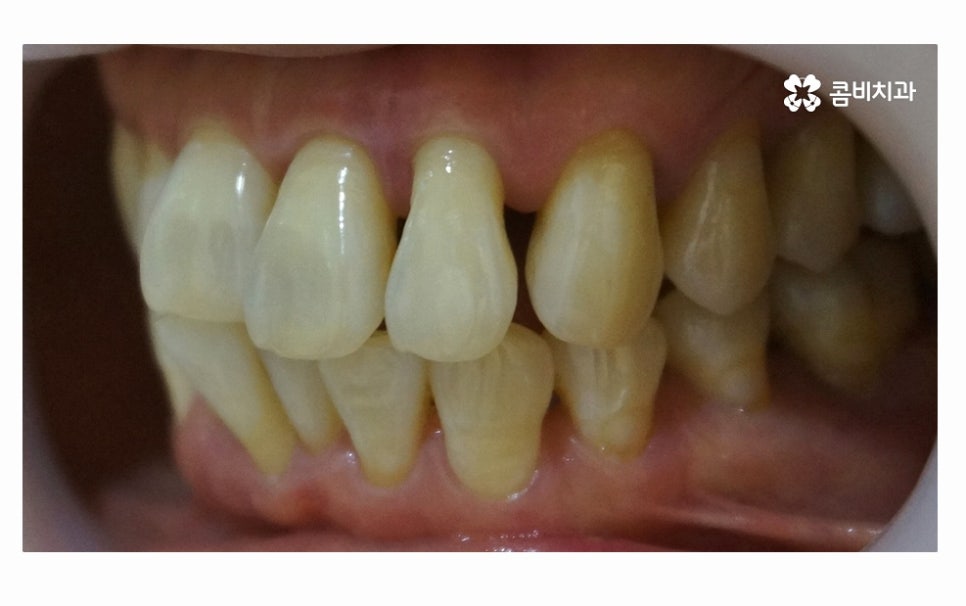

사진에서 보시는 것처럼 치아 사이에 빈 공간도 많고

잇몸이 내려앉아서 치아의 하단부도 많이 드러난 상태인데

치아를 잇몸이 제대로 감싸주지 못하고 이렇게

내려앉게 될 경우 치아도 많이 시리게 되고

치주염이 심해지는 단계에서는 치아가 흔들려서

식사도 제대로 하지 못할 정도로 어려움을 겪게 되실 수 있어요.

이처럼 잇몸질환이 심해지면 치아의 상실로 이어질 수 있고

잇몸이 퇴축되어 심미적으로도 좋지 않지만